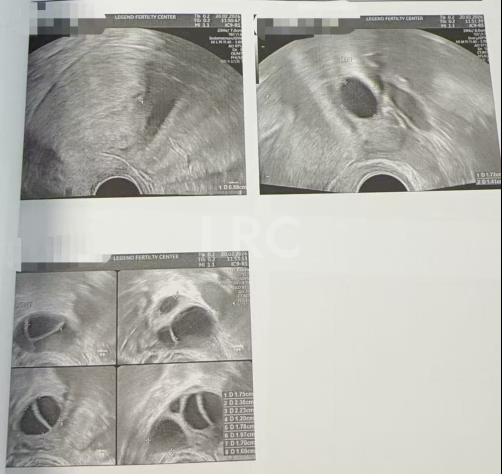

取卵及受精

取卵:7颗

成熟MII:6颗

- 未成熟卵泡:0颗

- 异常卵泡:1颗

ICSI受精:4颗

养囊成功:4颗

PGT-A染色体筛查结果

4 枚囊胚送检,2 枚过筛 - 适合移植